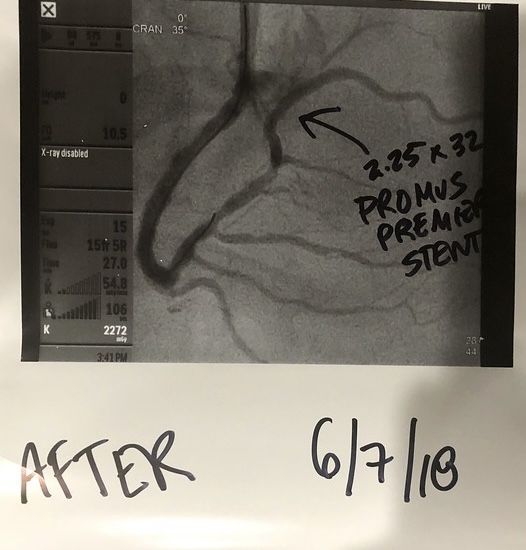

Surgeon wants to put in a couple of stents and look around to see what else he can fix....